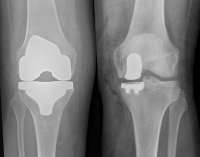

Partial and total knee replacement

Robotic joint replacement

Revision knee replacement